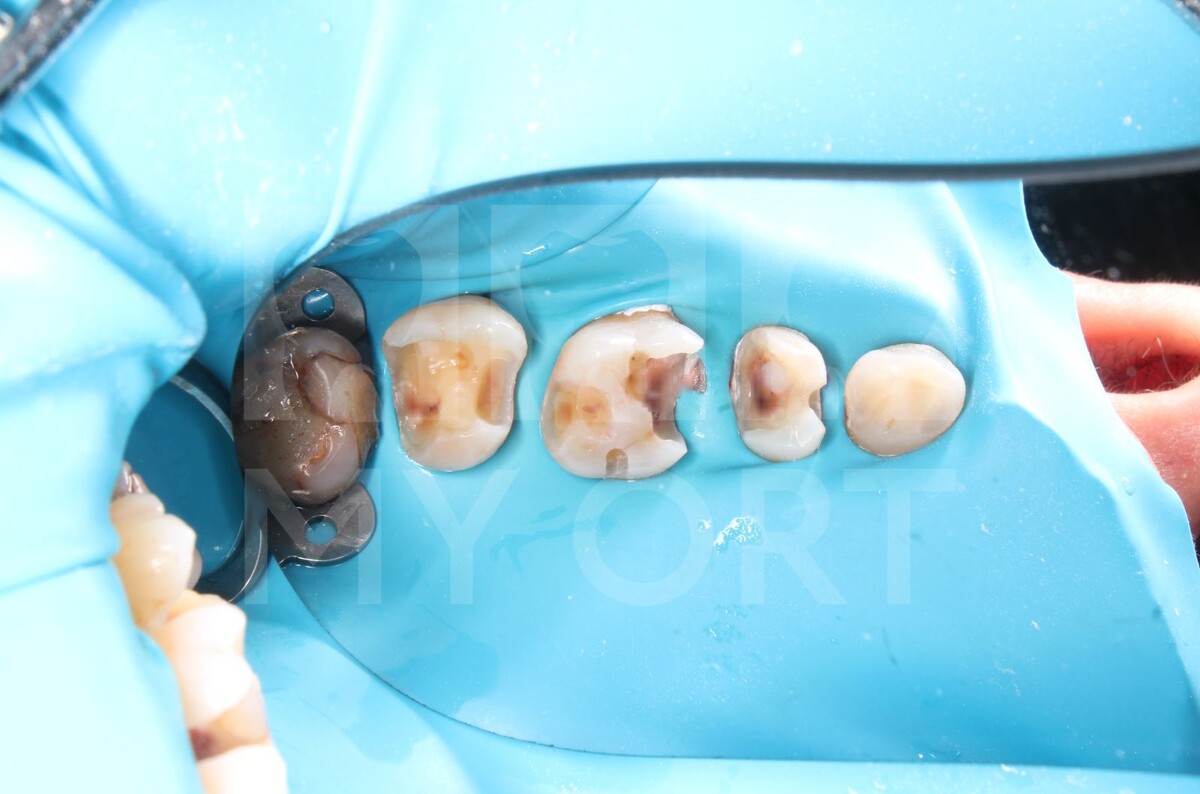

Просто посмотрите какой результат у нас получился, все жалобы по терапевтической части пациентки я смогла убрать.

Хочу отметить, что пациентке еще предстоит восстановление здоровья зубов, а именно - ортопедическое и хирургическое лечение (установка имплантатов и протезирование для восстановления функциональности зубного ряда).